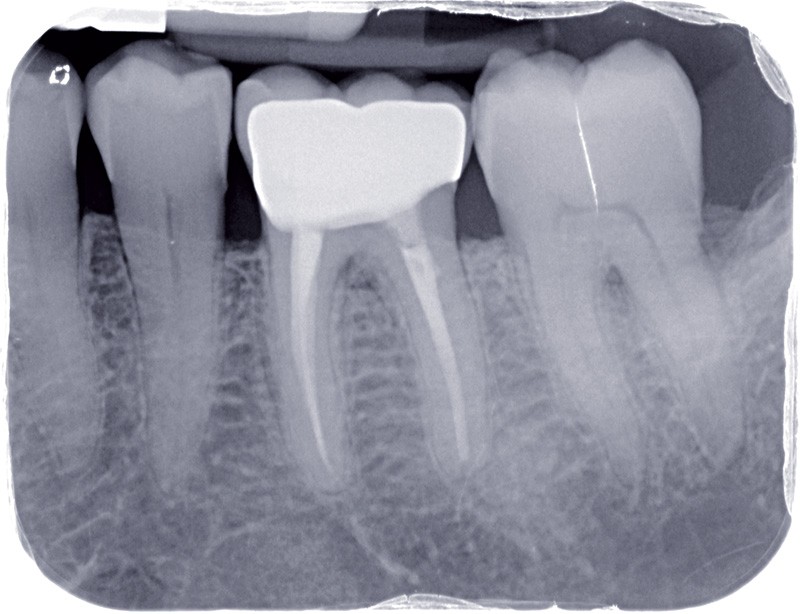

La dentisterie contemporaine privilégie les modes de restauration conservateurs avec pour objectif de préserver la vitalité pulpaire. Cependant, des échecs peuvent survenir du fait de nouvelles agressions et ce, malgré la qualité des procédures opératoires mises en œuvre (fig. 1).

Dans ces situations, le praticien est conduit à dépulper et à restaurer les dents traitées endodontiquement. Les traitements doivent alors s’inscrire dans le concept du continuum endo-restaurateur qui a été défini comme étant « le processus spatio-temporel sans interruption ni rupture qui débute par l’accès à l’endodonte et s’achève avec la mise en place de la restauration prothétique d’usage » (1). Il existe bien une continuité, du traitement endodontique à la restauration fonctionnelle d’usage qui conditionne le pronostic et les résultats du traitement à long terme (fig. 2).